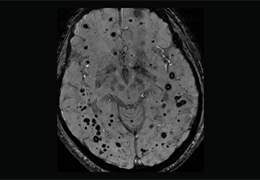

ART-Plan™ Artificial Intelligence Contouring